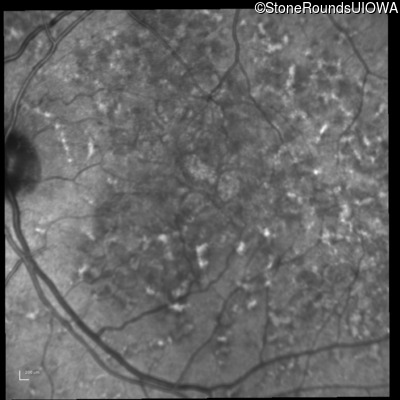

Age at visit: 49 years

This 49 year old man was first told he had a fundus abnormality on a routine eye exam at age 34. Ten years later he noticed some distortion just superior to fixation.

Pattern Dystrophy PRPH2 Gln239Stop CAG>TAG   AD